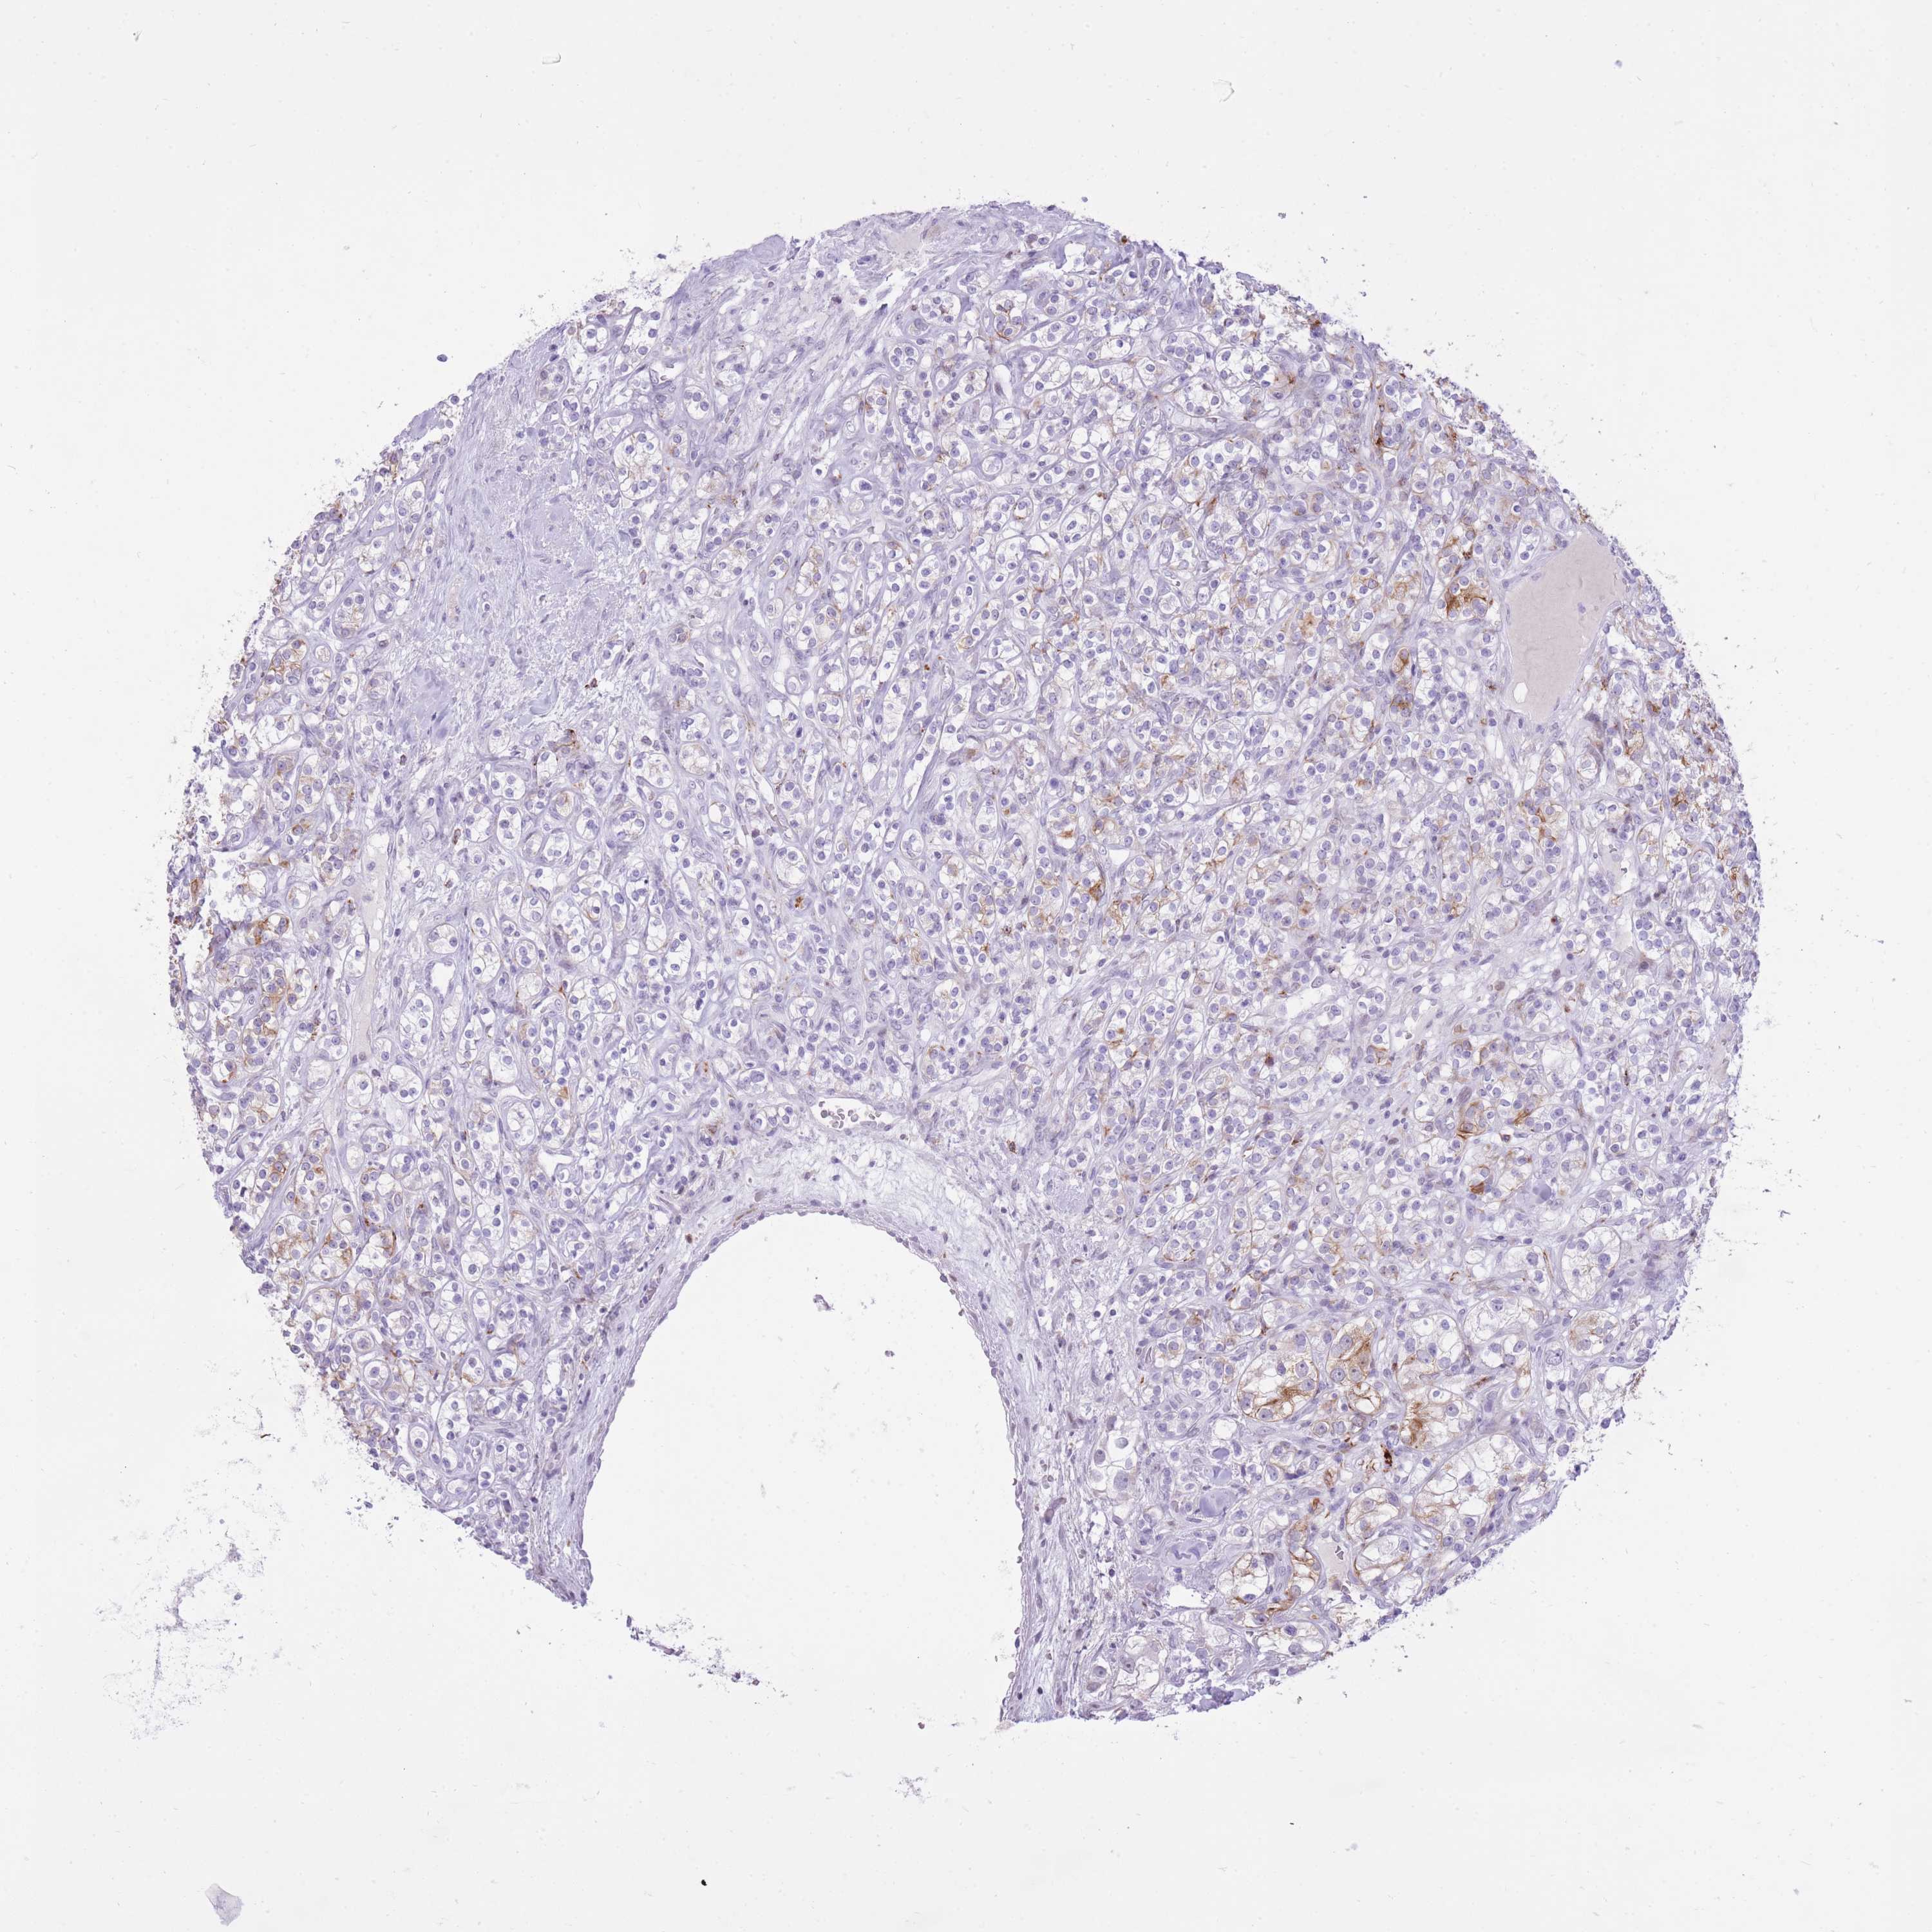

KIDNEY RENAL CLEAR CELL CARCINOMA (VALIDATION) - Interactive survival scatter ploti

The Survival Scatter plot shows the clinical status (i.e. dead or alive) for all individuals in the patient cohort, based on the same data that underlies the corresponding Kaplan-Meier plots. Patients that are alive at last time for follow-up are shown in blue and patients who have died during the study are shown in red.

The x-axis shows the expression levels (FPKM) of the investigated gene in the tumor tissue at the time of diagnosis. The y-axis shows the follow-up time after diagnosis (years). Both axes are complimented with kernel density curves demonstrating the data density over the axes. The top density plot shows the expression levels (FPKM) distribution among dead (red) and alive patients (blue). The right density plot shows the data density of the survived years of dead patients with high and low expression levels respectively, stratified using the cutoff indicated by the vertical dashed line through the Survival Scatter plot. This cutoff is automatically defined based on the FPKM cutoff that minimizes the p-score. The cutoff can be changed by dragging the vertical line or by entering a cutoff value in the square labeled "Current cut-off".

Under the Survival Scatter plot the p-score landscape (black curve; left axis) is shown together with dead median separation (red curve; right axis). Dead median separation is the difference in median mRNA expression between patients who have died with high and low expression, respectively. It is calculated as follows: median FPKM expression of dead patients with high expression - median FPKM expression of dead patients with low expression. This is intended to aid the user in visually exploring custom cutoffs and the associated p-scores and dead median separation.

Individual patient data is displayed and can be filtered by clicking on one or more of the category buttons on the top of the page. Categories describing expression level and patient information include: high, low, alive, dead, female, male and tumor stages. The scale of the x-axis can be toggled between linear and log-scale by clicking on the "x log" button. Mouse-over function shows TCGA ID, patient information and mRNA expression (FPKM) for each patient.

& Survival analysisi

Kaplan-Meier plots summarize results from analysis of correlation between mRNA expression level and patient survival. Patients were divided based on level of expression into one of the two groups "low" (under cut off) or "high" (over cut off). X-axis shows time for survival (years) and y-axis shows the probability of survival, where 1.0 corresponds to 100 percent.

MEIS3 is not prognostic in Kidney Renal Clear Cell Carcinoma (validation)

Best expression cut offi

Based on the FPKM value of each gene, patients were classified into two groups and association between prognosis (survival) and gene expression (FPKM) was examined. The best expression cut-off refers the FPKM value that yields maximal difference with regard to survival between the two groups at the lowest log-rank P-value. Best expression cut-off was selected based on survival analysis .

When clicking on this number, the vertical dashed line indicating cut-off, the interactive survival plot, and the Kaplan-Meier curve will be adjusted to show results based on the best expression cut-off.

: 6.44

P scorei

Log-rank P value for Kaplan-Meier plot showing results from analysis of correlation between mRNA expression level and patient survival.

N/A

TCGA RNA samplesi

RNA-seq data is reported as average FPKM (number Fragments Per Kilobase of exon per Million reads), generated by the The Cancer Genome Atlas (TCGA) .

Normal distribution across the dataset is visualized with box plots, shown as median and 25th and 75th percentiles. Points are displayed as outliers if they are above or below 1.5 times the interquartile range. FPKM values of the individual samples are presented next to the box plot.

Average pTPM 7.3

Number of samples 100